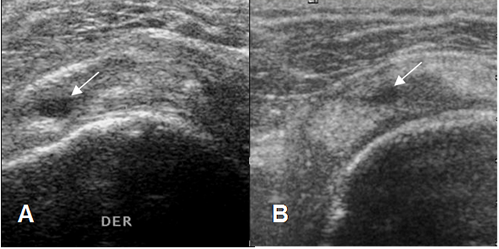

Fig 106. Pérdida de la convexidad del tendón.

Ecografía coronal. Pérdida de la concavidad superior del tendón supraespinoso, por ruptura parcial. (Flecha delgada). Normalmente el reborde del tendón es paralelo, a la cabeza del húmero. (Flecha gruesa).